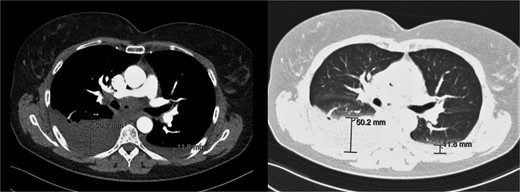

Additional imaging diagnostics with X-ray demonstrated bilateral pleural effusion, more apparent at the right side (Fig. 1). A subsequent computed tomography (CT) scan showed no signs of pulmonary embolism and confirmed the pleural effusion (Fig. 2). In addition, air was seen in the anterior mediastinum (pneumomediastinum). Both air and pleural effusion were attributed to normal healing after the recent VAMLA, and in the absence of clinical alarm symptoms the patient was sent home. In the absence of loculation or contrast captation, the bilateral pleural effusion had no radiological signs of empyema. One of the symptoms of pleural effusion is dyspnea which was also present in the patient. In addition, there was no suspicion of an infectious cause with normal vital values with a temperature of 37.7°C and no significant elevation of WBC or CRP. It was suspected that the effusion was postoperative or reactive to the suspected lung cancer. Regarding the hoarseness, the most likely cause was post-operative swelling of the surgical area. As the hoarseness did not occur immediately post-operative, iatrogenic recurrent nerve injury was not suspected.

CT-scan during visit to the emergency department confirming the pleural effusion attributed as reactive or postoperative.